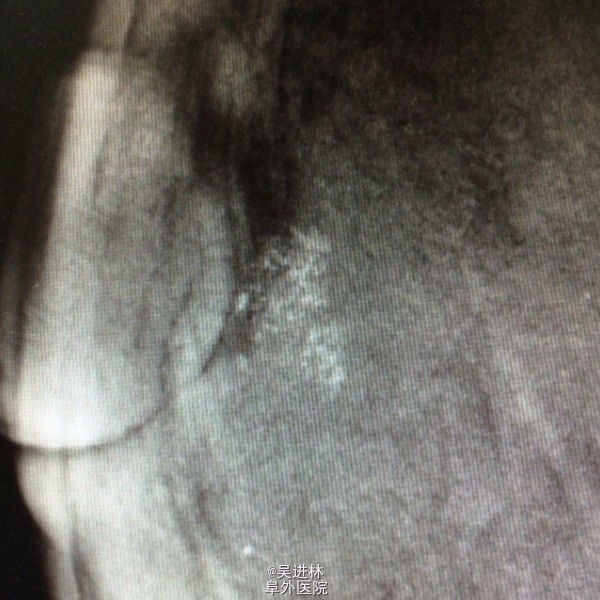

今天本来打算继续腹膜后脂肪肉瘤,但是悲闻姚贝娜因癌去世,遂借以下病例来谈谈乳腺癌钙化特点:患者中年女性,慢性起病,双侧乳房肿物4年余,以“双侧乳腺癌可疑”收入院。一般女性绝经候乳腺腺体开始萎缩,而此人腺体高度发达,脂肪组织几乎不可见,也是令人称奇(见钼靶)。查体双乳均可触及肿块,质硬,境界清,无压痛,表面欠光滑。腋下淋巴结未触及。钼靶显示双侧均可见簇状钙化。术前几乎被当作双侧乳腺癌来教学查房了一番,术后病理提示乳腺腺病。